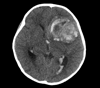

Results: Median age at diagnosis of six patients was 7.6 years. Tumours originated in the cerebral cortex (n = 2) or diencephalon (n = 4). Three patients presented with acute, massive haemorrhage and three had leptomeningeal dissemination at diagnosis. Paediatric e-GB had the typical histological characteristics seen in adult tumours. Universal immunoreactivity for INI1 and lack of diverse protein expression were seen in all cases. One tumour had a chromosome 22q loss. Three tumours (50%) harboured a BRAF: p.V600E. One thalamic tumour had an H3F3A p.K27M. All patients received radiation therapy with (n = 3) or without chemotherapy (n = 3). All patients experienced tumour progression with a median survival of 169 days. One patient with nonmetastatic disease had early leptomeningeal progression. Two patients had symptomatic tumour spread outside the central nervous system (CNS) through a ventriculoperitoneal shunt. One additional patient had widespread metastases outside the CNS identified at autopsy.